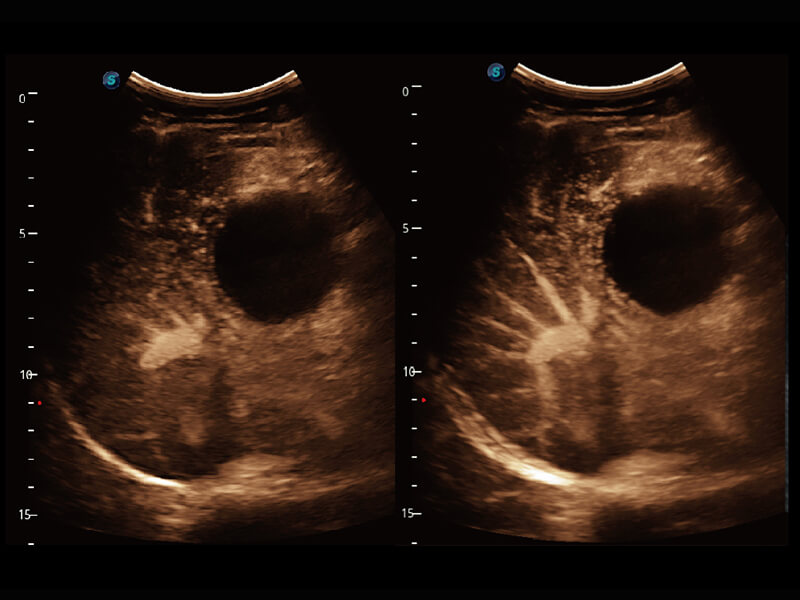

性能优异的硬件架构,极大提升超声系统的运行效率和数据处理能力。相比以往超声成像系统,Wis+平台为您带来极快的响应速度和成像帧频,提升检查流畅度。

超宽频带技术,为容积成像带来优质的二维图像基础,为您呈现丰富的结构细节,栩栩如生地展示宝宝的宫内形态以及各种组织的立体结构。